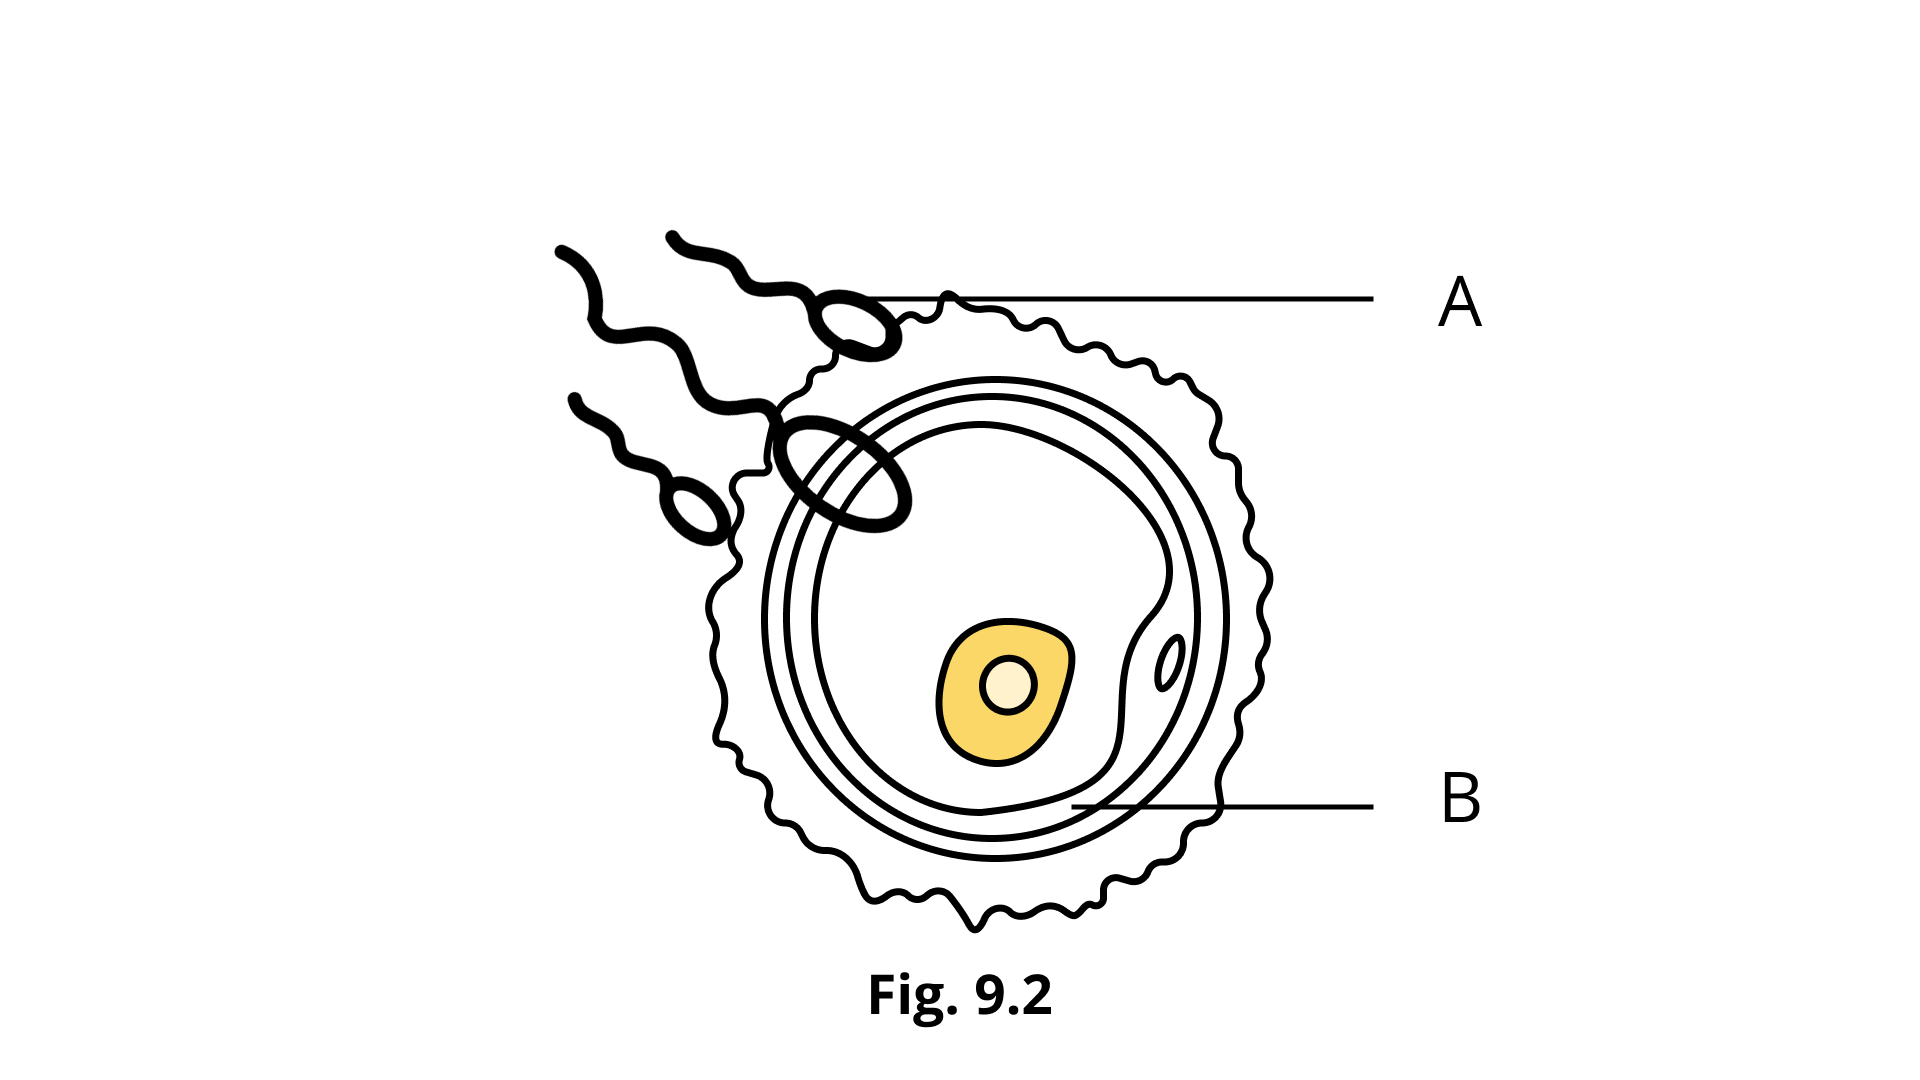

1. What is Ovulation?

The function of releasing eggs from the ovaries is called ovulation. This occurs when the follicle has fully expanded and achieved its maximum size, accompanied by the collection of fluids within the follicle without a considerable increase in pressure. The stigma, or macula pellucida, emerges as a little oval-shaped patch jutting outward as a clear cone area when the follicle grows out and later experiences localized changes in color, integrity, and transparency. The maximal level of estrogen hormone release occurs just before ovulation. Ovulation happens at the stigma site after a rise of luteinizing hormone. This surge is required for ovulation to occur. Ovulation separates the. It follicle from the ovum, which is enclosed by the corona radiata by releasing follicular fluid. In the presence of spermatozoa, the cells of the corona radiata will separate later.